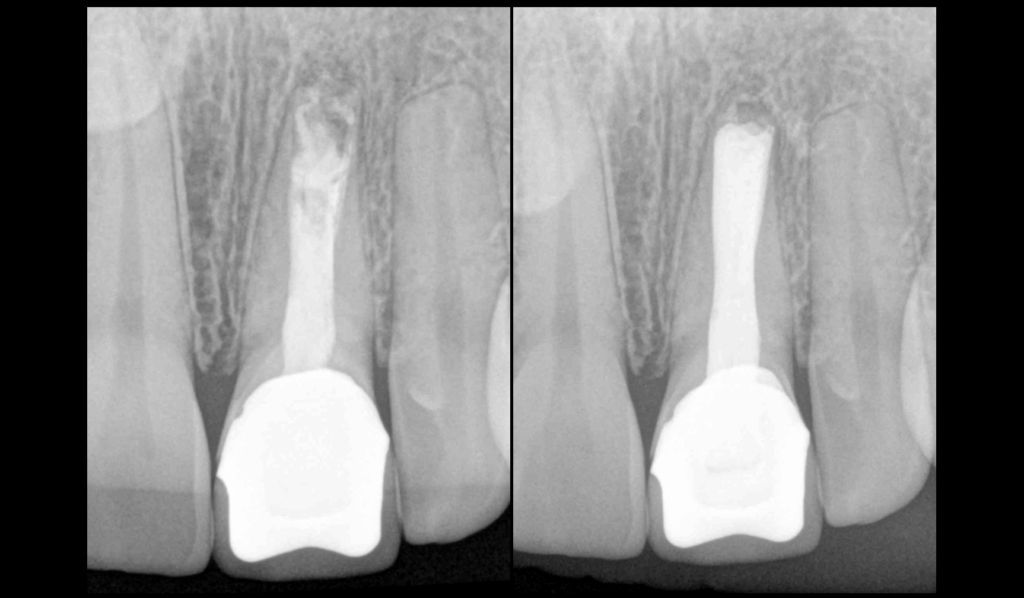

❓𝐐𝐮𝐞𝐥𝐥𝐞 𝐞𝐬𝐭 𝐯𝐨𝐭𝐫𝐞 𝐭𝐞𝐜𝐡𝐧𝐢𝐪𝐮𝐞 𝐝’𝐨𝐛𝐭𝐮𝐫𝐚𝐭𝐢𝐨𝐧 𝐩𝐫𝐞́𝐟𝐞́𝐫𝐞́𝐞 𝐩𝐨𝐮𝐫 𝐥𝐞𝐬 𝐃𝐏𝐈 ?

🟡 Obturation verticale à chaud ?

🟡 Bouchon de biocéramique + obturation verticale à chaud ?

🟡 Bouchon de biocéramique + monocone à froid ?

🟡 Bouchon de biocéramique + thermocompaction ?

🟡 Thermocompaction ?

🟡 Cône moulé + ciment biocéramique ?